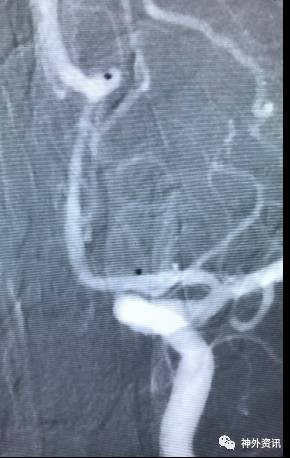

微导管成袢技巧

适用于:

(1)颈内动脉-眼动脉段的Carotid Cave动脉瘤

(2)大脑前动脉A1起始段的偏下方指向动脉瘤

(3)其他载瘤动脉近心端走行方向与动脉瘤指向之间大于90度的微导管到位

塑型要点:

(1)基于载瘤动脉走向与动脉瘤指向的微导管塑型,并适当增加微导管头端的直行长度,有助于成袢和微导管稳定性

(2)可利用颈内动脉分叉或大脑中动脉M1分叉进行微导管成袢

病例一

眼动脉动脉瘤,支架完全释放后,微导管成袢逆行到位